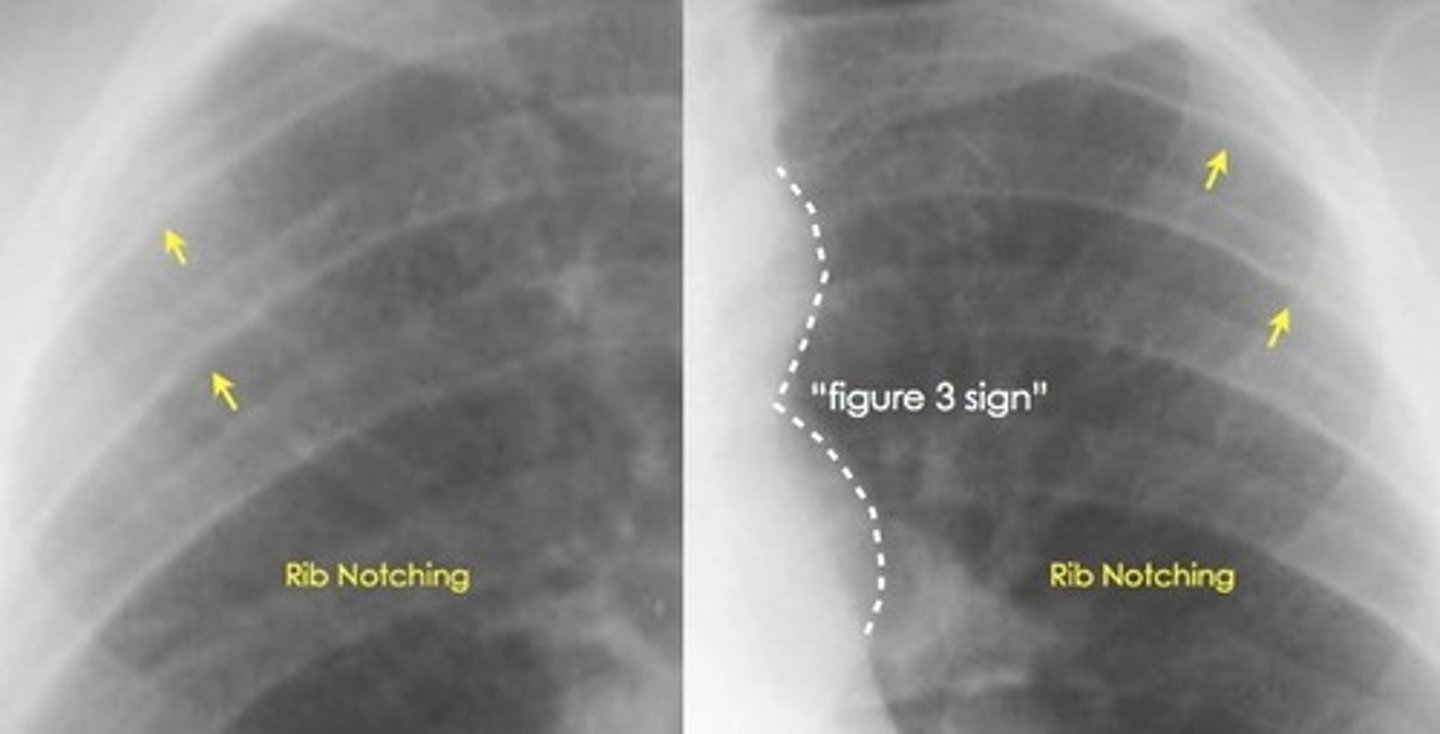

What are 2 characteristic CXR signs of coarctation of the aorta?

Figure 3 sign; inferior notching of the ribs